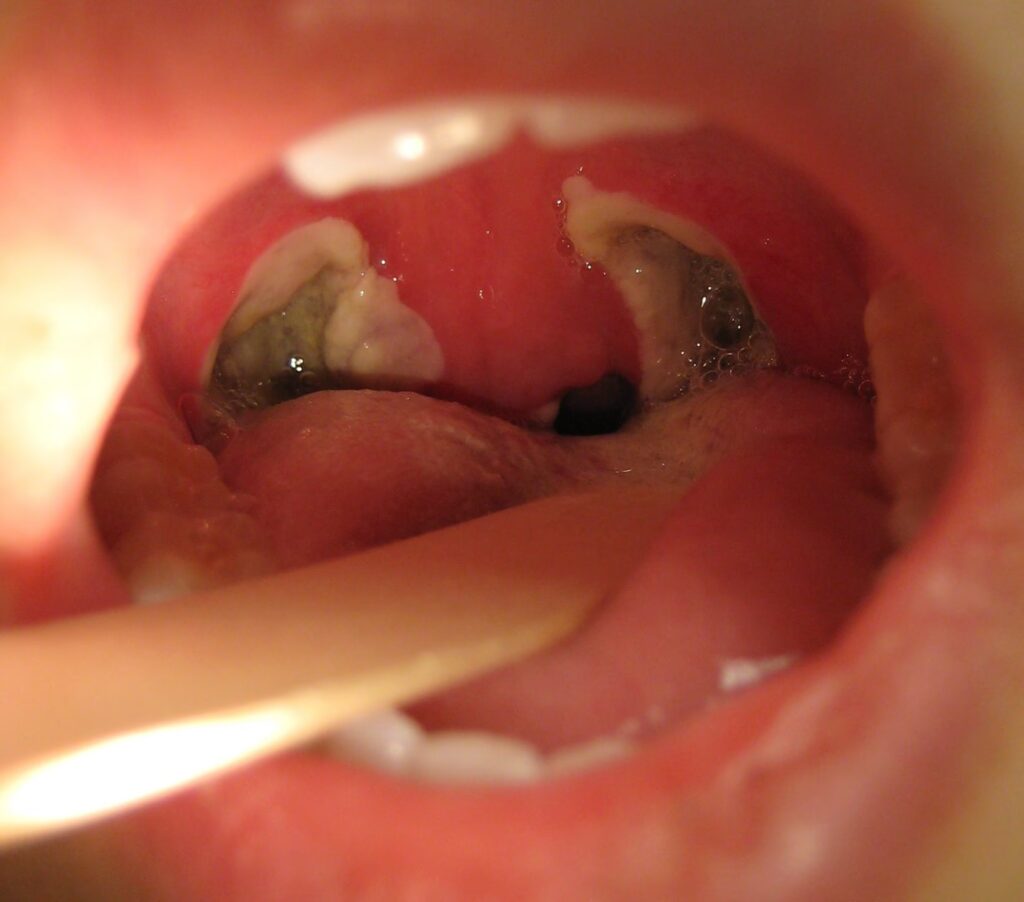

Mange mennesker, især børn, oplever problemer med deres mandler. Disse to små, ovale vævspuder bagerst i halsen er en del af immunsystemets første forsvarslinje, men nogle gange kan de selv blive kilden til problemer. Forstørrede mandler kan føre til vejrtrækningsbesvær, især om natten, og gentagne infektioner kan forringe livskvaliteten betydeligt. En kirurgisk fjernelse af mandlerne, kendt som en tonsillektomi, er en velkendt procedure, der kan afhjælpe disse problemer. Tidligere blev operationen primært udført for at behandle kronisk halsbetændelse, men i dag er den mest almindelige årsag at behandle søvnrelaterede vejrtrækningsproblemer forårsaget af forstørrede mandler.

Dette er i dag den hyppigste årsag til operationen, især hos børn. Mandler kan blive forstørrede efter gentagne infektioner, eller de kan simpelthen være naturligt store. Når mandlerne er så store, at de delvist blokerer luftvejene, kan det føre til en række problemer:

Kirurgen holder munden åben med et specielt instrument og fjerner mandlerne. Der findes flere metoder til dette: